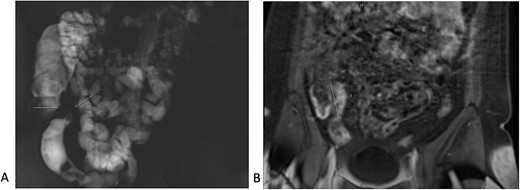

A 34-year-old female presented with colicky episodic abdominal pain and symptoms suggestive of subacute small bowel obstruction in the setting of known stricturing CD. Her symptoms were poorly controlled on multiple medications—Azathioprine, Mesalazine, Adalimumab and Budesonide. She had no previous history of abdominal surgery or gynaecological pathology. She had twice undergone endoscopic balloon dilatation of a terminal ileal stricture with short-lived symptomatic relief. Contrast-enhanced computed tomography (CT) of the abdomen and pelvis showed a short segment of acute inflammation of the terminal ileum (Fig. 1) and an incidental right adnexal cyst. Pelvic ultrasonography was normal. Magnetic resonance enterography confirmed stricturing CD with two segments of inflammation of the terminal ileum (lengths of 5 and 3.8 cm) approximately 5 cm from the ileocaecal valve (Fig. 2).

Computed tomography scan (portal venous phase post intravenous contrast) showing a short segment of thickened, enhancing terminal ileum consistent with terminal ileitis of CD.

Magnetic resonance enterography demonstrating strictures of the small bowel (A) in a segment of terminal ileitis with acute inflammation (B).